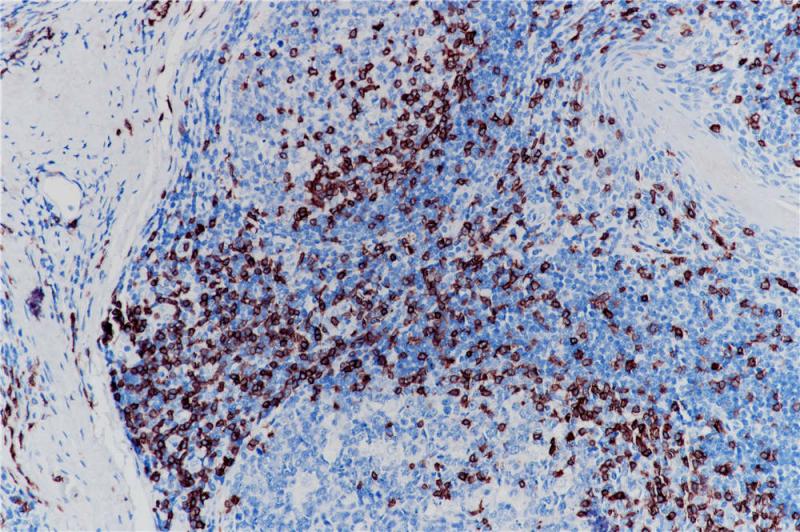

Bcl-2是分子量为25kDa的线粒体内膜蛋白,是一种细胞凋亡的抑制因子,参与细胞凋亡的调控。Bcl-2正常表达于套区和边缘区的小B细胞和部分T细胞、胸腺髓质细胞和正常乳腺上皮细胞。在多数软组织肿瘤中阳性表达,如孤立性纤维瘤、滑膜肉瘤等。该抗体也用于滤泡性淋巴瘤与反应性滤泡增生的诊断及鉴别诊断。

扁桃体、滤泡性淋巴瘤